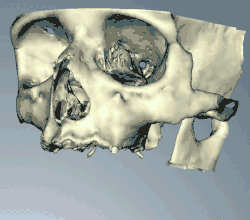

CT scans can be loaded to CAD/CAM software to create a simulation of the desired treatment. Virtual implants are then placed and a stent created on a 3D printer from the data.

When a more exacting plan is needed beyond clinical judgment, the dentist will make an acrylic guide (called a stent) prior to surgery which guides optimal positioning of the implant. Increasingly, dentists opt to get a CT scan of the jaws and any existing dentures, then plan the surgery on CAD/CAM software. The stent can then be made using stereolithography following computerized planning of a case from the CT scan. The use of CT scanning in complex cases also helps the surgeon identify and avoid vital structures such as the inferior alveolar nerve and the sinus.[49][50]: 1199